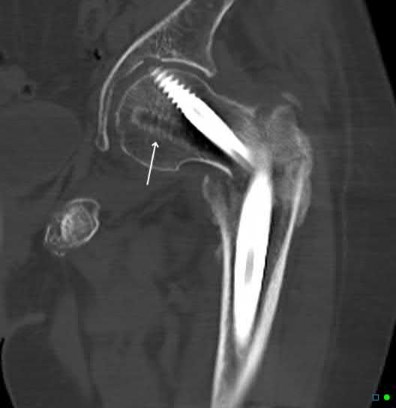

A 12-year-old obese boy presents with vague left thigh and knee pain. He is diagnosed with a Slipped Capital Femoral Epiphysis (SCFE) as seen in similar clinical scenarios. During percutaneous in-situ fixation, unrecognized penetration of the guide wire into the hip joint occurs. What is the most likely specific complication resulting from this technical error?

Correct Answer: Chondrolysis

Explanation:

Chondrolysis is a severe complication of SCFE characterized by rapid destruction of the articular cartilage. While it can occur idiopathically, its most established iatrogenic cause is unrecognized intra-articular hardware penetration. The 'approach-withdraw' fluoroscopic technique is required during pinning to assure pins are entirely intraosseous. Avascular necrosis (AVN) is usually due to damage to the epiphyseal blood supply (retinacular vessels) secondary to the initial displacement, forceful closed reduction, or posterosuperior pin placement.